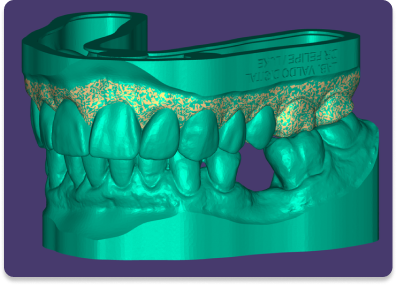

planejamento digital

A tecnologia está mudando a maneira como a odontologia é praticada, e uma das mais recentes inovações é o scanner intraoral.

O processo de digitalização é muito mais rápido do que os moldes tradicionais.

Com sua precisão, conforto e rapidez, é uma opção atraente para pacientes e dentistas em busca de um tratamento odontológico mais avançado, eficiente e consequentemente menos oneroso.